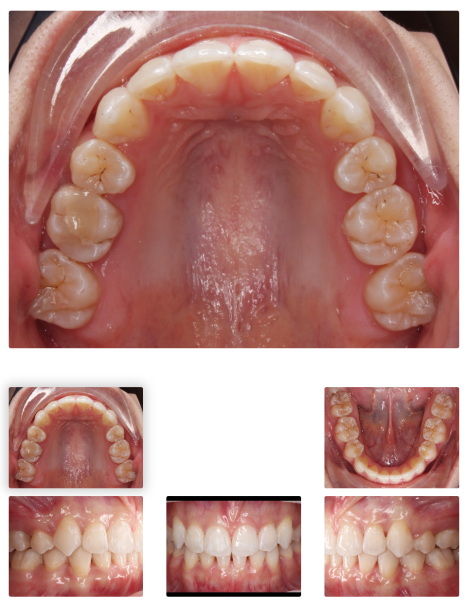

< 인비절라인 돌출입 교정 사례 중 일부>

조경*님 치료기간: 24.09.02 - 25.03.04 (약 1년 6개월)